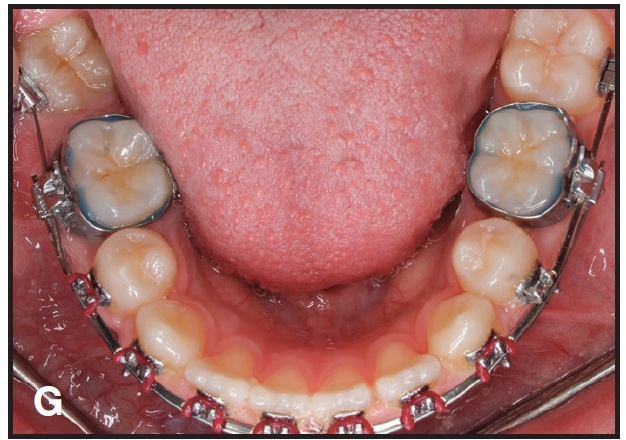

This technique is demonstrated in a 13-year-old female patient with an impacted lower right second molar (D). A U-loop spring was activated after surgical exposure of the tooth (E). Two months later, the second molar had been partially uprighted (F). After three more months of uprighting, the spring was removed and a continuous archwire was placed (G). It took another three months to completely upright the molar using straightwire mechanics, with no side effects on the anchor units (H).